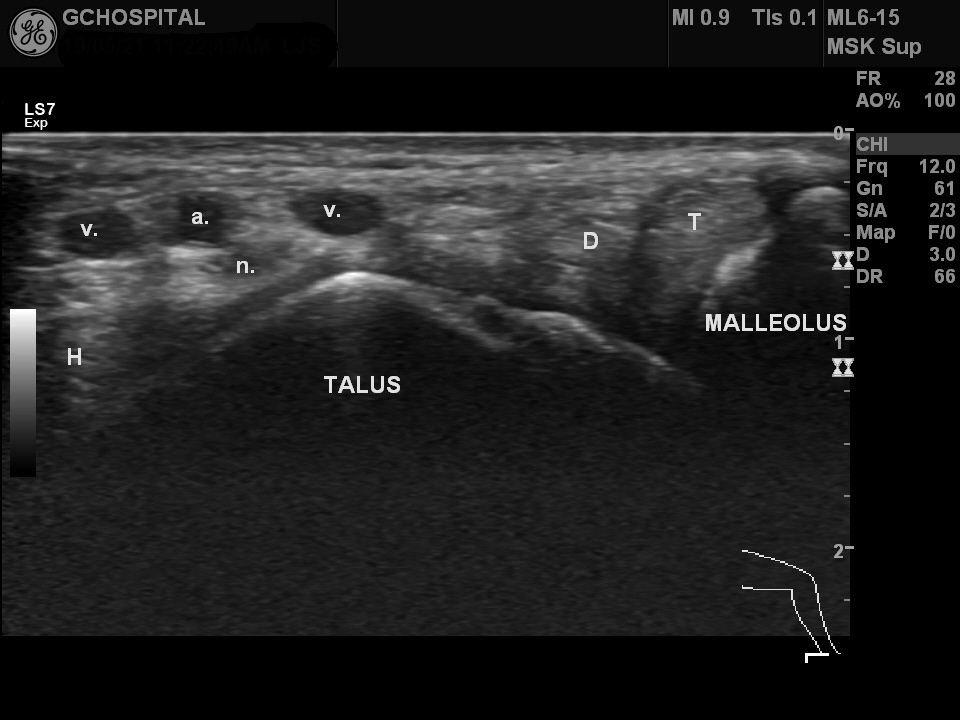

T : tibialis posterior tendon

D : flexor digitorum longus tendon

H : flexor hallucis longus

a. : posterior tibial artery

v. : posterior tibial veins

n. : posterior tibial nerv

위의 영상은 내측 복사뼈와 talus bone이 함께 보이도록 좀 더 아래에서 찍은 초음파영상입니다. tibialis posterior & flexor digitorum longus tendon은 앞으로 빠져서 발바닥으로 향하고, 나머지 구조물들은 발꿈치쪽을 향해 뒤로 빠지면서 갈라지고 있습니다. 이 레벨에서는 flexor retinaculum이 더이상 보이지 않습니다.

발목의 초음파를 실시할 때에는 이러한 각 구획별 해부학을 이해하면서, 탐촉자를 어떤 높이에 댔을 때 어떤 구조물들이 존재하는가를 미리 짚어두고 있는게 필요합니다.